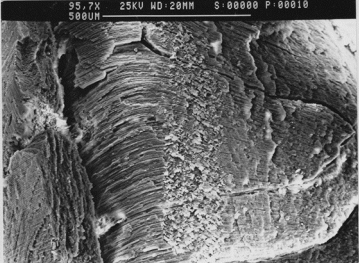

The finestructure of the normal human lens shows concentrical arranged lensfibers with radial composition one layer after the other. So the normal lens is perfect made for changing the form due to their elasticity. The SEM picture shows the arrangement of the lensfibers but between the fibers there are connections which strongly reduce the elasticity. Different layers are connected together which further will reduce the elasticity. We found no cortical swelling but degenerated fibers with large spaces between the remaining cortex and nucleus. As seen at the slitlamp -with the different coloured regions starting at the old embryonic central inner nucleus with dark brown colour decreasing up to the outer nucleus and cortex- we can see this analog to the SEM pictures.

fig. 3, fig 4   Inner Nucleus, lamellar structure

These embedded half nuclar parts show the typical lamellated bands of the lensfibers and broken region especially at the aequator.

In the degenerated region edge and groove patterns are visible.

The interfibrillare connections seem to be weaken, so that waterclefts  in between showing the border of the different lens parts but also the harder inner part of the nucleus.

((This is important for us during surgery. The waterclefts as well as the border of different parts of density of the cataractlens will allows us special surgery options and strategies.))

Fig 5: Inner Nucleus, lamellarconcentrical structure higher magnifacation with roseleaf similar composition of the concentrical lensfiberlayers.

This embedded inner nuclear  shows on the one hand the typicall lamellated bands of the lensfibers but also on the other hand a roseleaf-similar structure and threedimensional composition of the lensfibers itself. (fig 5)

Fig 9: Higher magnification : Border between different parts of the outer nucleus, lamellar-concentrical structure with parallel lensfibers, numerous thin layers

Fig 10: Detail view: Higher magnification : Border between different parts of the outer nucleus, lamellar-concentrical structure with parallel lensfibers, numerous thin layers.